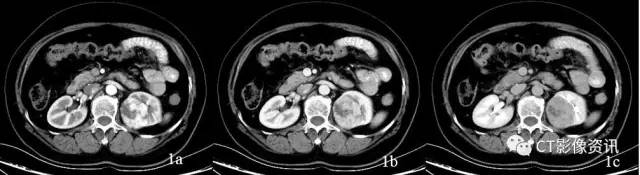

病例资料 患者女性,58岁,既往体健,查体发现左肾占位,行泌尿系CTU扫描,左肾占位呈典型“快进快出”强化方式(图1),考虑肾癌,透明细胞癌可能性大。左肾上腺见结节灶,呈明显均匀强化(图2),肾上腺转移瘤待排,行能谱CT检查。

图2:左肾上腺见一结节灶,三期强化CT值分别为63Hu、82Hu、91Hu,呈渐进性强化,转移瘤?原发肿瘤?